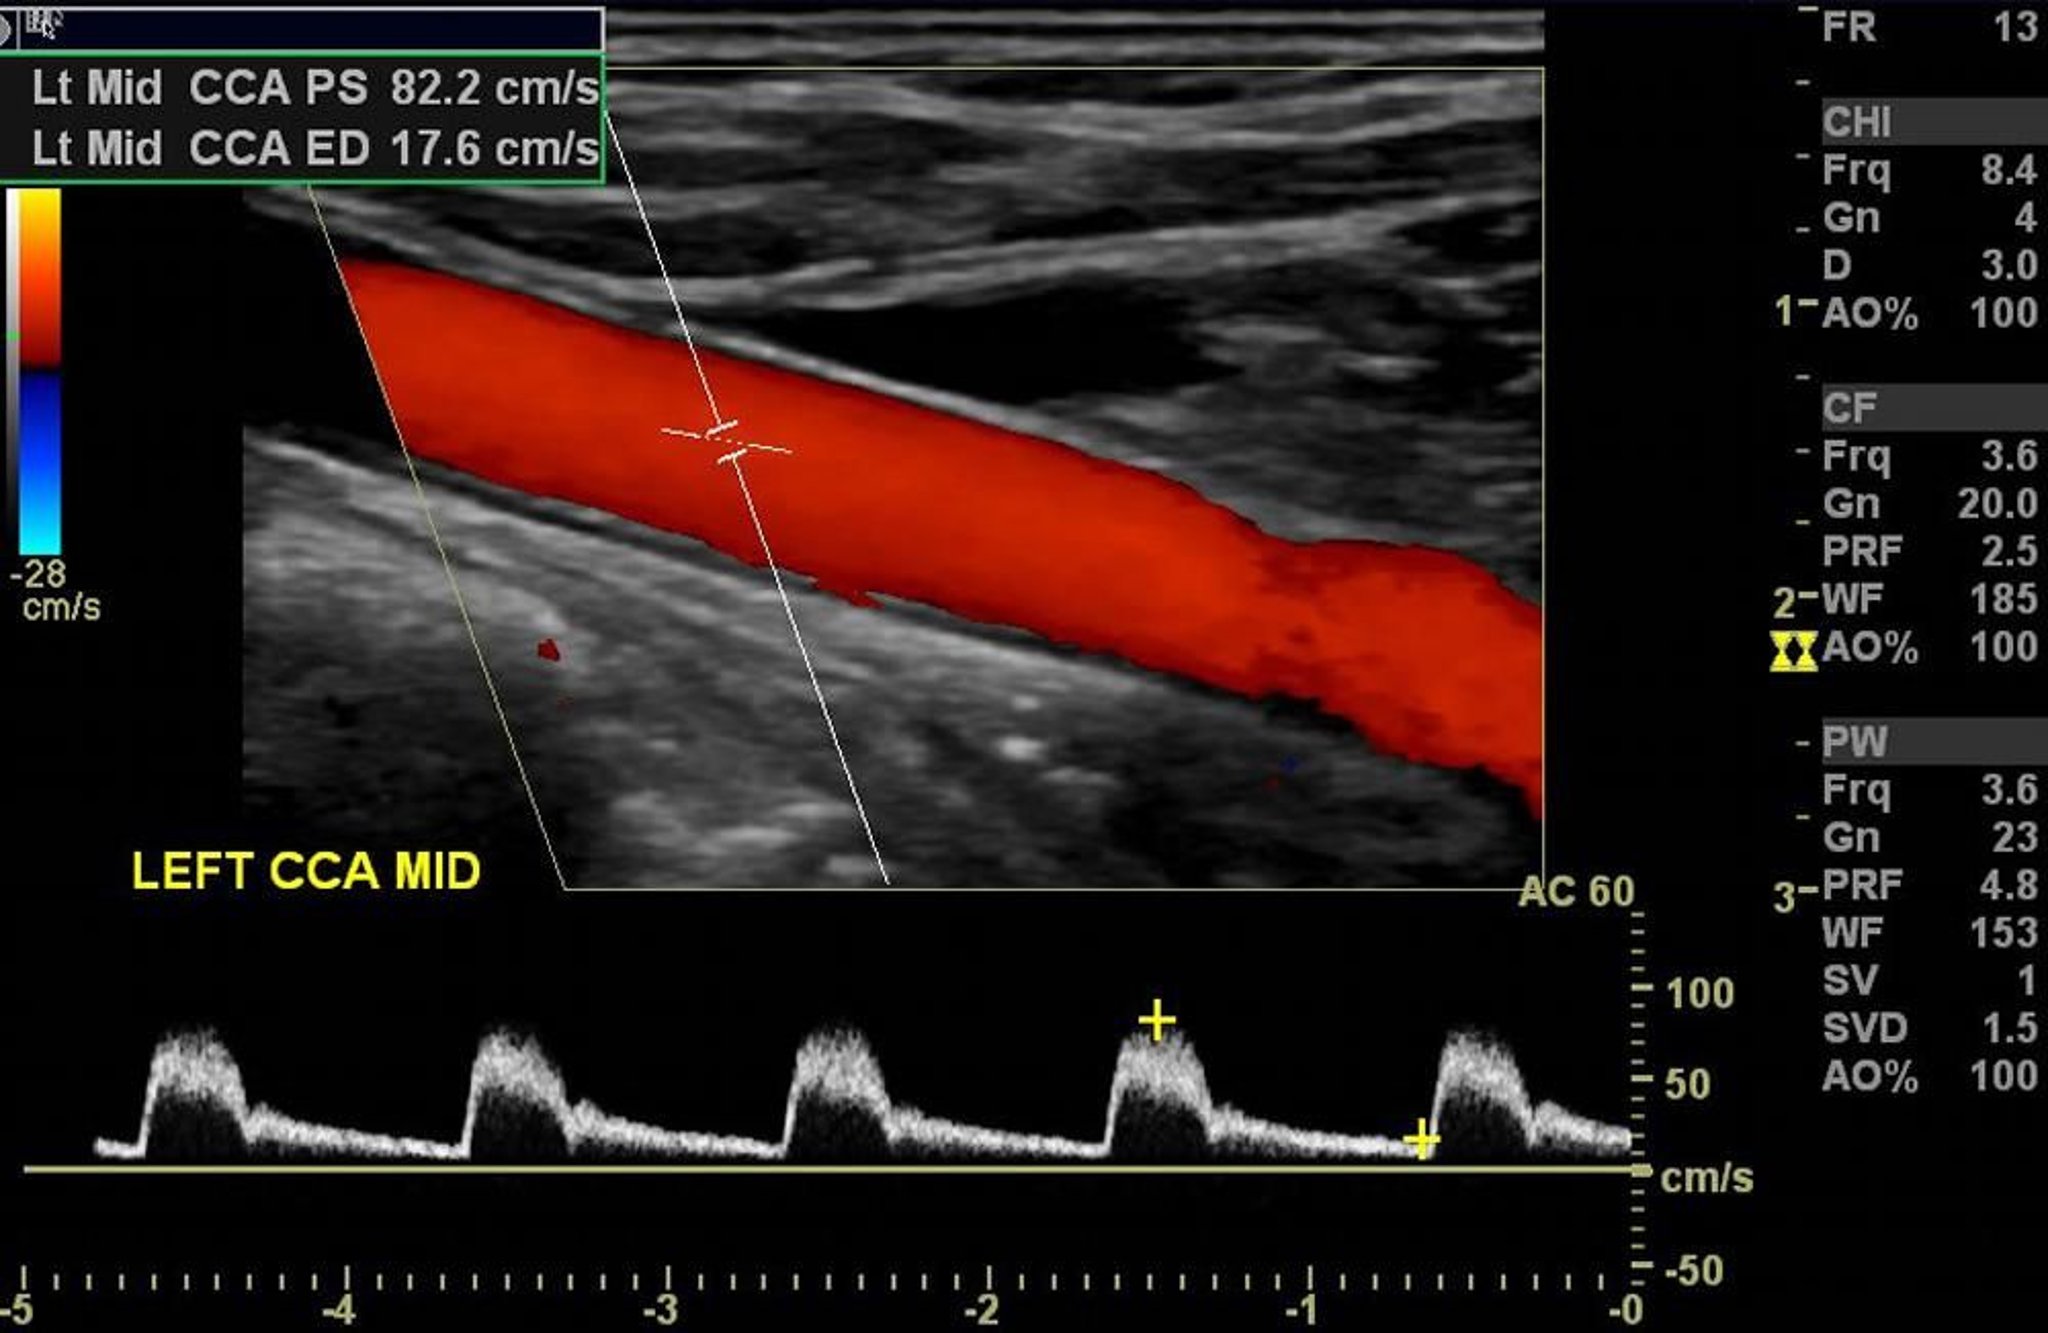

Die Farbdoppler-Ultraschalluntersuchung der linken Halsschlagader zeigt einen normalen arteriellen Fluss ohne signifikante Verengung.

Image courtesy of Hakan Ilaslan, MD.